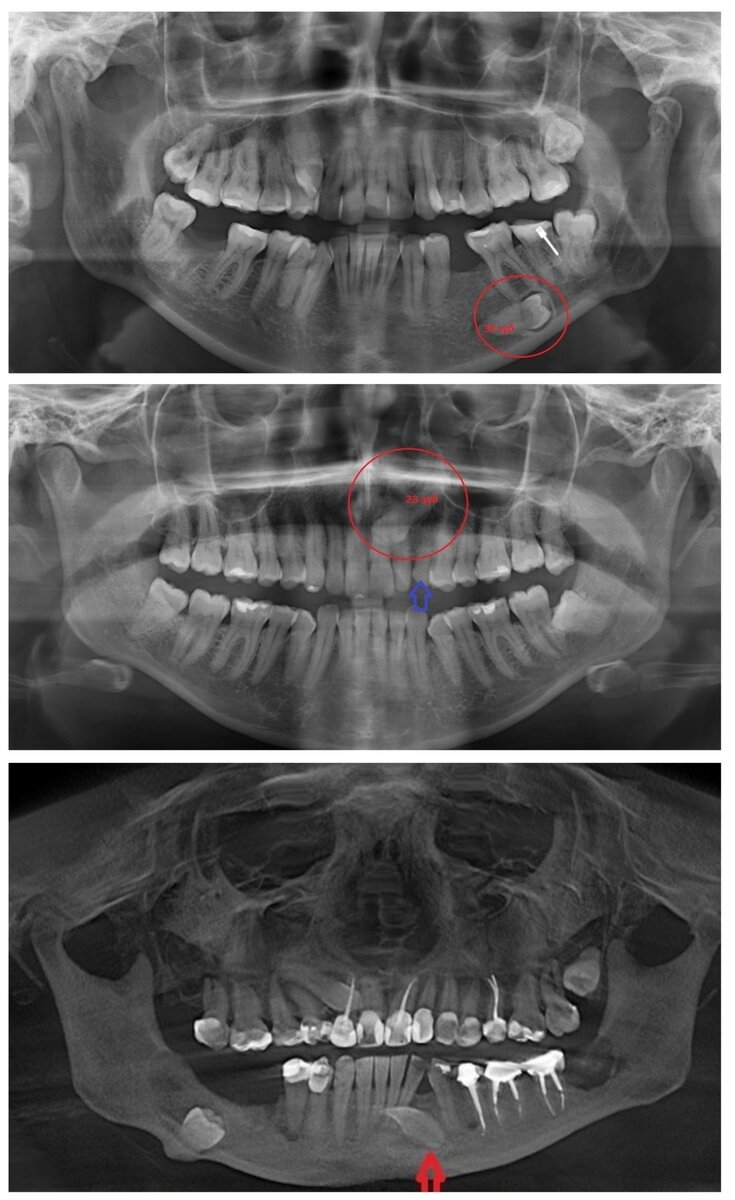

Найти полностью ретинированные зубы – это настоящий квест. Их может быть вообще не видно, потому что они расположились под существующими элементами зубного ряда. В таком случае вариант диагностики только один: необходимо делать полный снимок челюсти, на котором будет отлично видно всю картину. Ниже на картинке – подборка примеров. Ретинированные зубы отмечены красным или стрелками.

Примеры ретинированных зубов на рентгеновском снимке